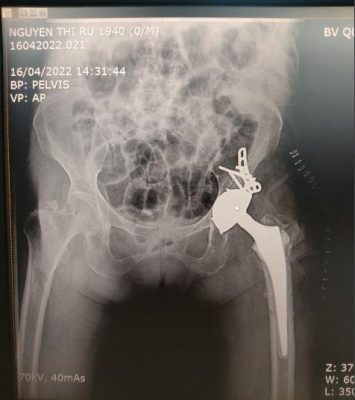

Thất bại sau kết xương gãy Thay khớp háng sau thất bại sau kết xương

liên mấu chuyển xương đùi gãy liên mấu chuyển xương đùi liên mấu chuyển xương đùi